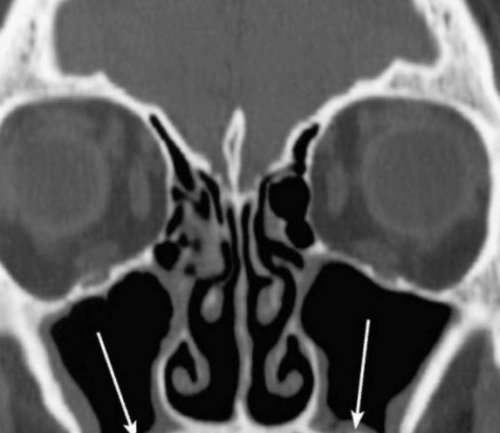

(кровью?) левой верхнечелюстной пазухи, повреждение носовой перегородки

гнойными массами или синусе воспаления нет, и он заполнен

помощью специального прибора